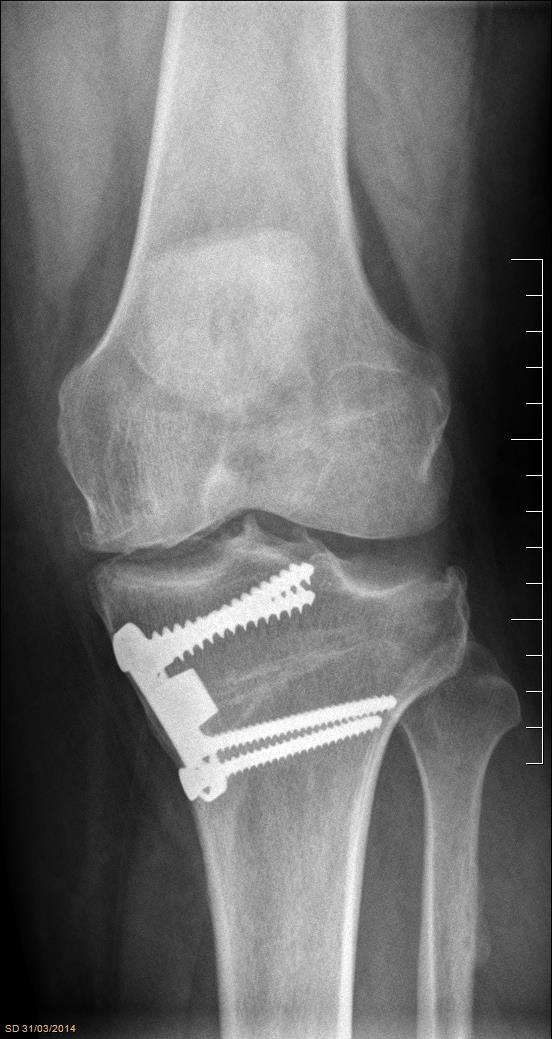

Trasplante osteocondral autólogo para tratar lesiones osteocondrales de la rodilla: evaluación de 62 pacientes con un seguimiento promedio de ocho años. [Osteochondral autograft transplantation for the treatment of osteochondral injuries of the knee: evaluation of 62 patients with an average follow-up of 8 years.]